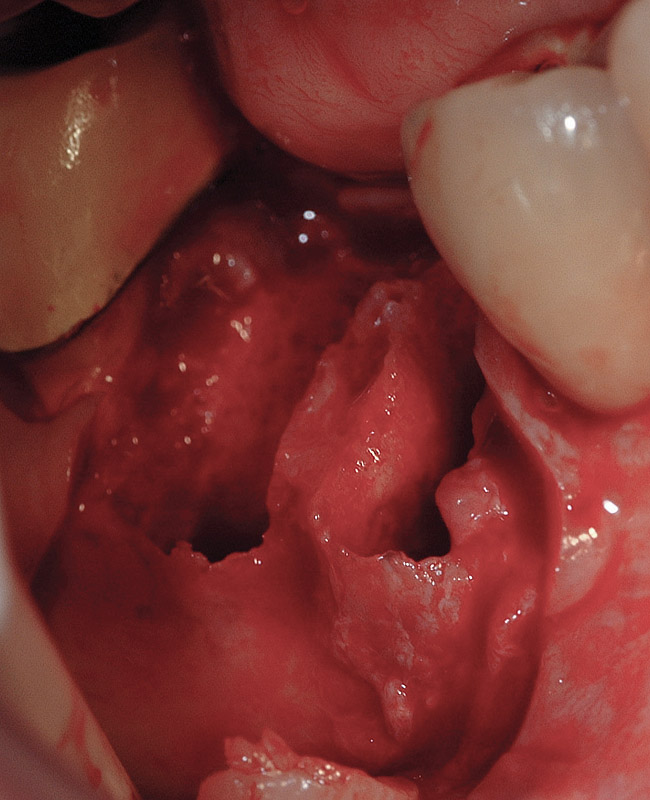

3. Extraction of a hopeless mandibular molar, defect debridement, and placement of an implant in one of the root sockets, followed by restoration with a molar-sized crown. This approach addresses the concern of two implants being placed closely together in the root extraction sockets. However, this treatment appropriately results in a mesial cantilever of the implant restoration and an area of potential plaque accumulation (Figure 1).

Figure 1  An implant has been placed in the mesial root socket at the time of mandibular molar extraction. The subsequent restoration demonstrates a significant cantilever and is not conducive to effective home care efforts.

Figure 1